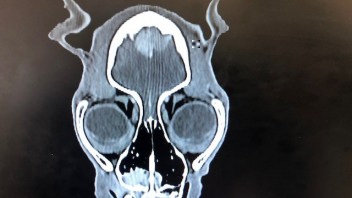

Mein Kater hat leider durch einen Zufallsbefund die Diagnose Hirntumore bekommen. Balou ist 15 Jahre alt und deshalb würde ich mich gegen eine OP entscheiden. Nun habe ich bereits sehr oft gelesen das man alternativ mit Vtalpilzen behandeln könnte.. Mit dem Agaricus Blazei und dem Maitake.